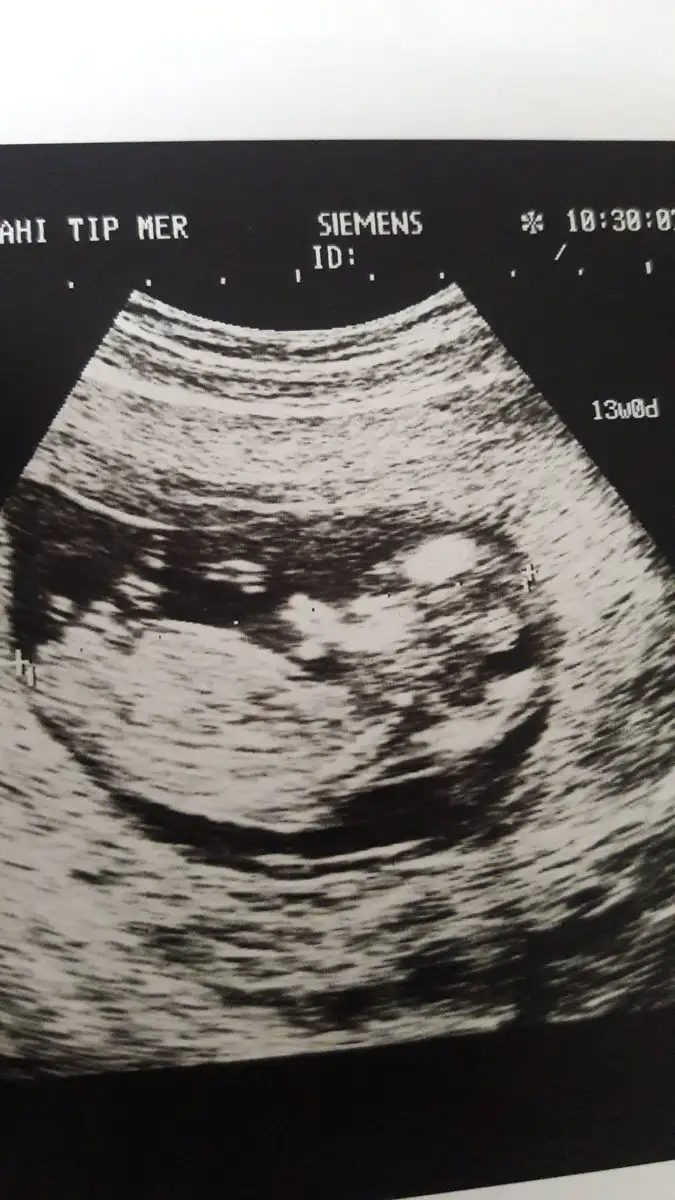

13 haftalık kızlar bana da yorum yaparmısınız

• IMG-20181224-WA0002-1.webp

54,2 KB · Görüntüleme: 208